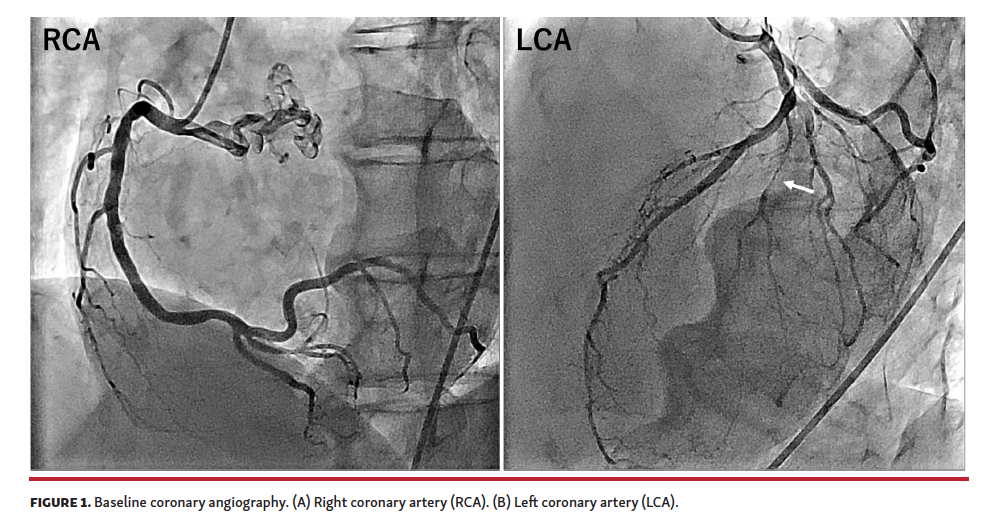

A 59-year-old man with a 95% stenosis in his diagonal branch (Figure 1) and no stenosis in the right coronary artery (RCA) or left circumflex artery was scheduled for percutaneous coronary intervention. A balloon angioplasty followed by a drug-coated balloon application achieved an acceptable result (Figure 2A, 2B). After prophylactic intravenous cefazolin administration for Proglide-site infection prevention, he started feeling general itching with palmar and cheek redness without any hemodynamic compromise, which resulted in methylprednisolone administration. However, ST elevation appeared in the inferior leads (Figure 3B), suggesting a potential RCA spasm. From these circumstances, a diagnosis of type I Kounis syndrome (KS) was made. Despite 2 puffs of nitroglycerin, the ST elevation persisted when bradycardia and hypotension progressed, and he became unconscious. While giving him intravenous epinephrine to maintain his hemodynamics, the ST level recovered, and he became fully conscious. When he complained of chest pain, a new ST elevation was noticed in the lateral leads, with ST levels in the inferior leads turning into depression (Figure 3C). Repeat angiography demonstrated neither spasm nor occlusion in the RCA (not shown), while the diagonal branch was completely occluded at the proximal portion (Figure 2C), which was considered to be responsible for ST elevation in the lateral leads. At that point, a diagnosis of type II KS was made. A drug-eluting stent implantation successfully restored blood flow (Figure 2D) and electrocardiographic changes returned to baseline (Figure 3D). Subsequently, his intradermal test was positive for cefazolin. This is the first reported case that combined 2 variants of KS in a single event.